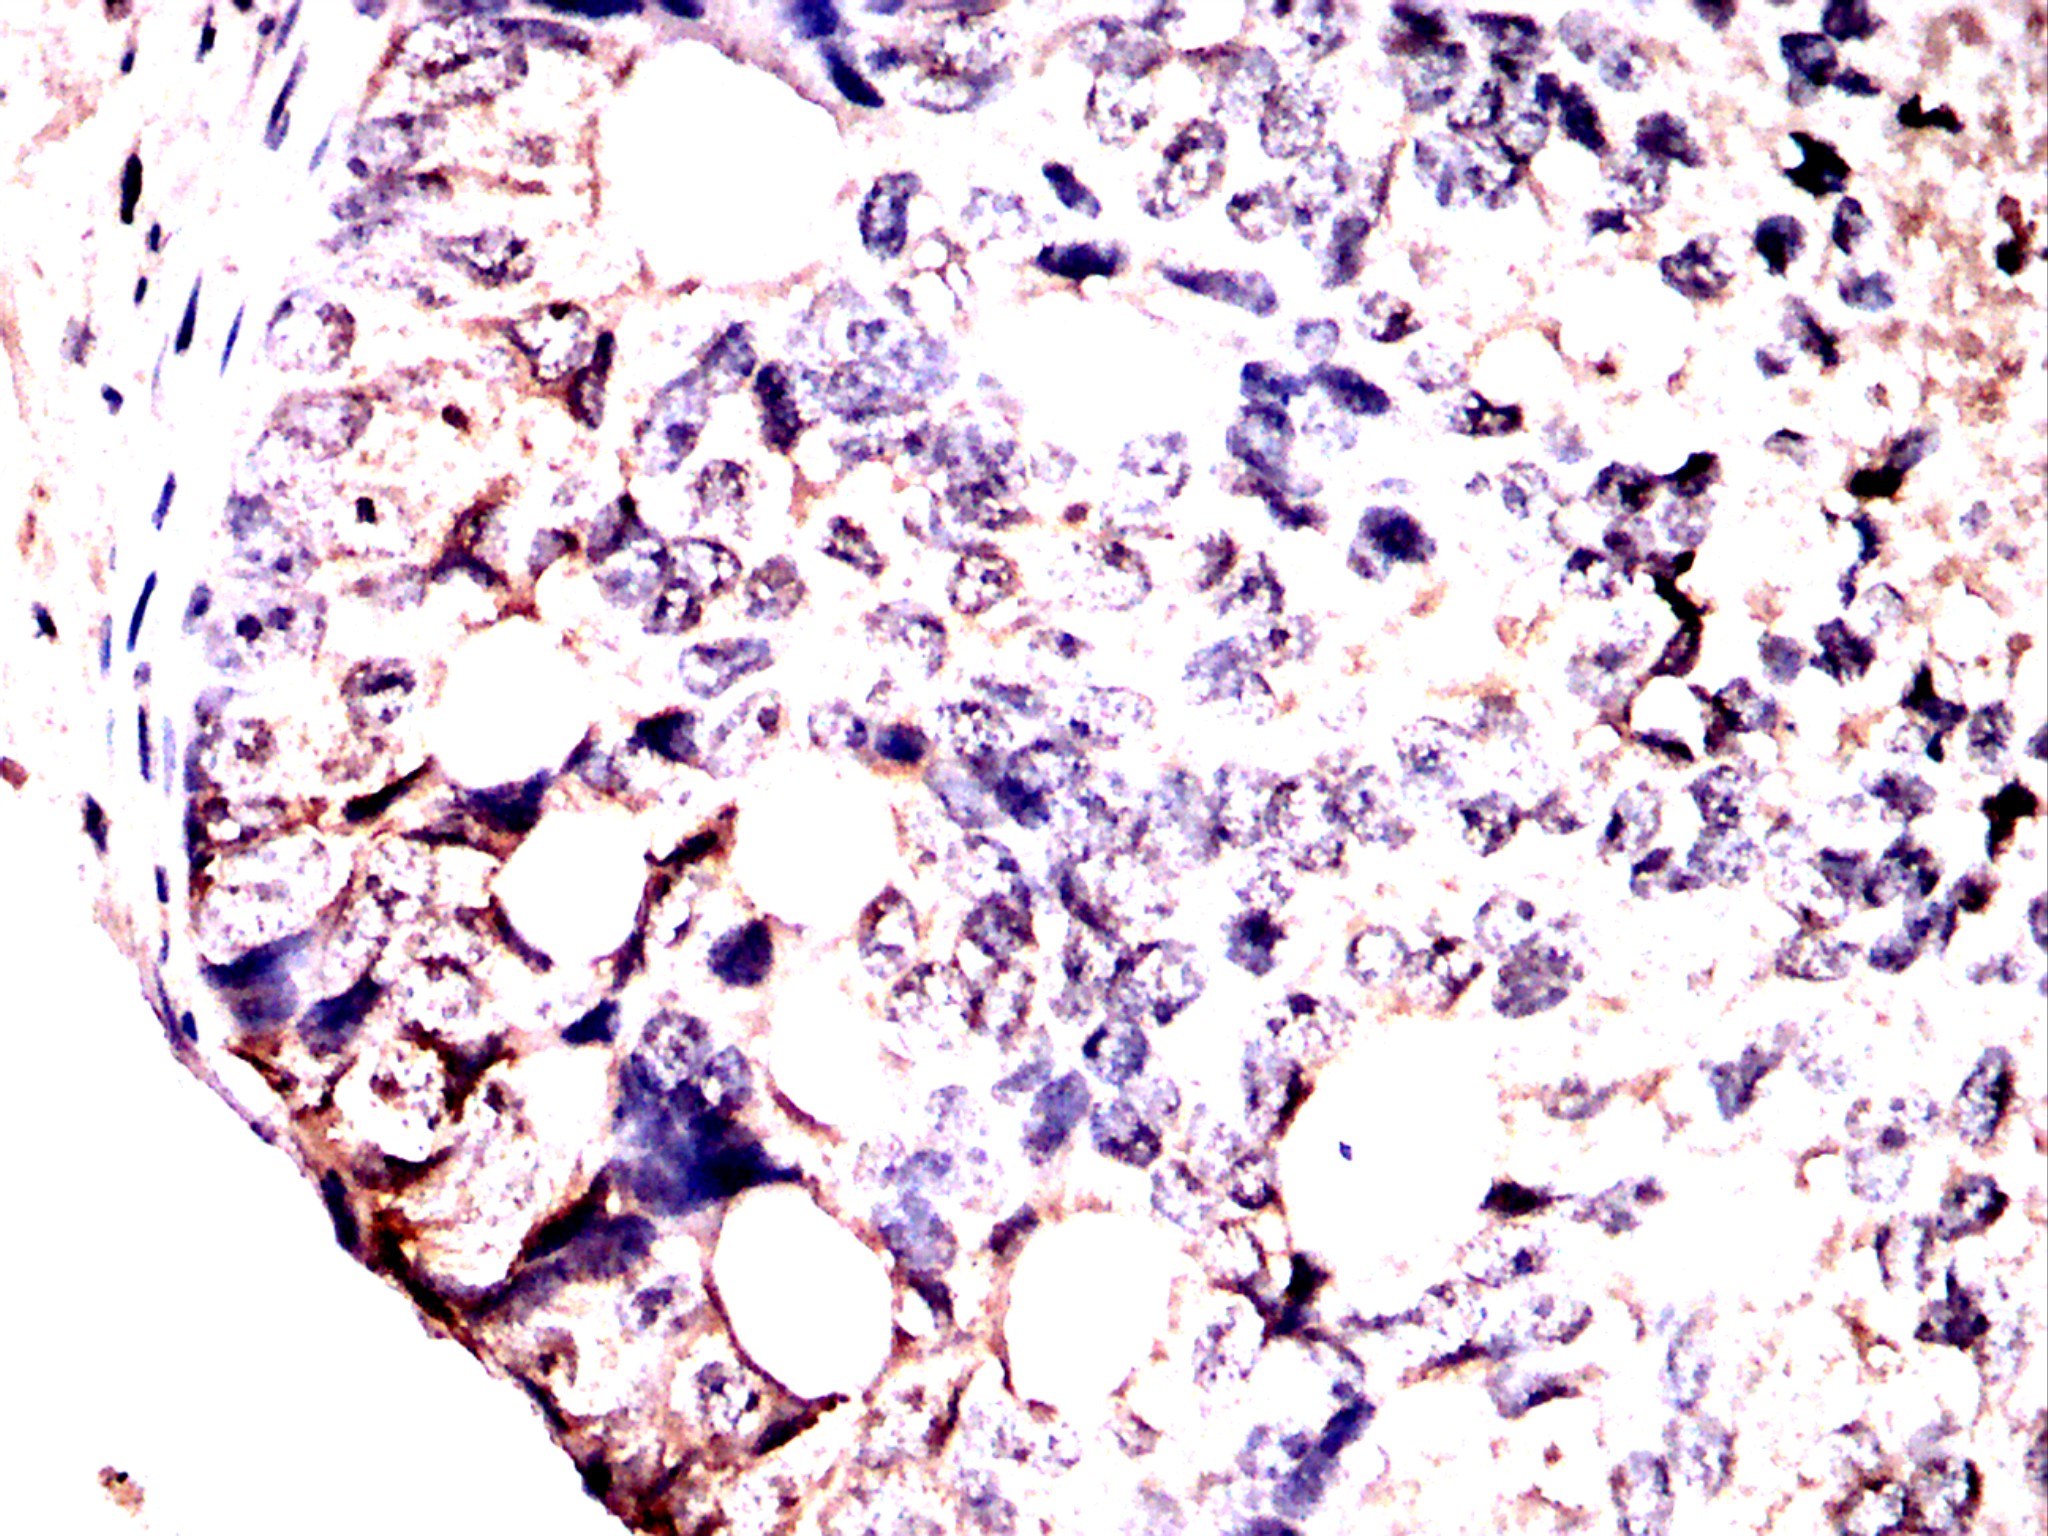

Immunohistochemical analysis of paraffin-embedded cervical cancer tissues using CBX1 antibody with DAB staining. Pre-treat the sections with heat-mediated antigen retrieval using sodium citrate buffer (pH 6.0) (OM750020) for 2 minutes. Wash the sections with ddH₂O and PBS (OM750003). Block the tissue with 10% non-immune goat serum(OM760028) at room temperature for 30 minutes. Incubate the tissue with the primary antibody diluted at a ratio of 1:1500 at 4°C overnight. At room temperature, dilute the secondary antibody, Goat Anti-Rabbit IgG(H&L)-HRP (OM644332), at a ratio of 1:200 and incubate for one hour. Use DAB(OM760029)as the chromogenic agent. Counterstain the tissue with hematoxylin, and mount the tissue sections with neutral gum.IHC

Immunohistochemical analysis of paraffin-embedded cervical cancer tissues using CBX1 antibody with DAB staining. Pre-treat the sections with heat-mediated antigen retrieval using sodium citrate buffer (pH 6.0) (OM750020) for 2 minutes. Wash the sections with ddH₂O and PBS (OM750003). Block the tissue with 10% non-immune goat serum(OM760028) at room temperature for 30 minutes. Incubate the tissue with the primary antibody diluted at a ratio of 1:1500 at 4°C overnight. At room temperature, dilute the secondary antibody, Goat Anti-Rabbit IgG(H&L)-HRP (OM644332), at a ratio of 1:200 and incubate for one hour. Use DAB(OM760029)as the chromogenic agent. Counterstain the tissue with hematoxylin, and mount the tissue sections with neutral gum.